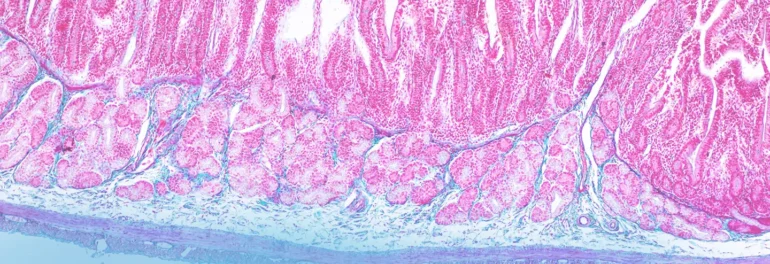

In addition to adding other cell types, we are also pursuing models to replicate the full 3D architecture of the intestine. One of our biomedical engineers is developing what we refer to as a “3D crypt model” that mimics the villi and crypts in the gut, creating texture. By forming gradients of nutrients from the top to the bottom in the crypt, we have been able to observe stem cells at the bottom and differentiated cells at the top, indicating that this model recapitulates the cell renewal and differentiation capacity of the gut in vivo.